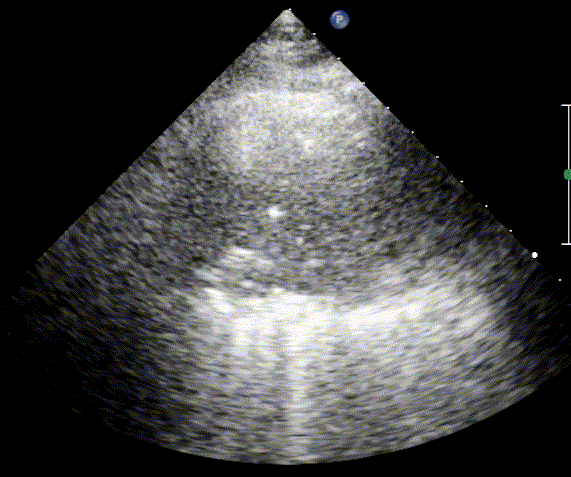

B-lines

For the cardiologist, the primary application of lung ultrasound is the assessment of B-lines. These vertical, laser-like reverberation artifacts arise from the pleural line and extend to the bottom of the screen without fading. B-lines move synchronously with respiration (lung sliding), erase underlying A-lines, and share the same echogenic intensity as the pleural line.

When fluid or inflammatory exudate accumulates in the lung interstitium, ultrasound waves reverberate between air–fluid interfaces, generating B-line artifacts. The presence of more than two B-lines per intercostal space indicates that the lung tissue is no longer fully air-filled. While few isolated B-lines may be seen in healthy lungs (lung fissures may cause few B-lines), the appearance of three or more B-lines within a single intercostal space is considered pathological.

Confluent B-lines

Cardiogenic Pulmonary Edema

In cardiogenic pulmonary edema, the presence of three or more B-lines per intercostal space together with preserved lung sliding on both sides is characteristic. As edema worsens and air content decreases, B-lines increase in number, become broader and confluent, and may fill the entire lung field, producing an appearance of an almost uniformly bright (“white”) lung. The number and density of B-lines correlate closely with the severity of pulmonary congestion.